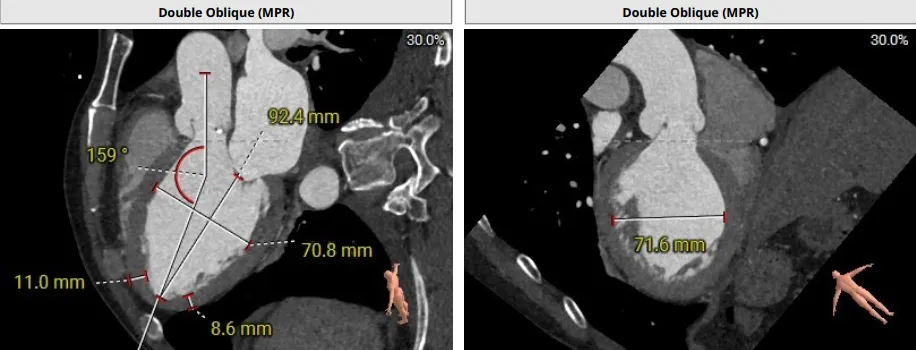

患者为主动脉瓣三叶瓣,瓣叶增厚,瓣叶未见明显钙化,存在三个瓣窦,窦部增大,分布较均匀;主动脉瓣环周长折算直径29.4mm;双侧冠脉开口高度可LCA:10.9mm,RCA:17.2mm;双侧冠脉未见明显钙化;最佳投射角度:右窦中心体位:CRA:16°/LAO:13°(其它参考角度如下图); 模拟切口位置:第6-7肋间;模拟输送器角度为143°;室间隔基底部稍增厚;升主动脉人工血管置换术后。